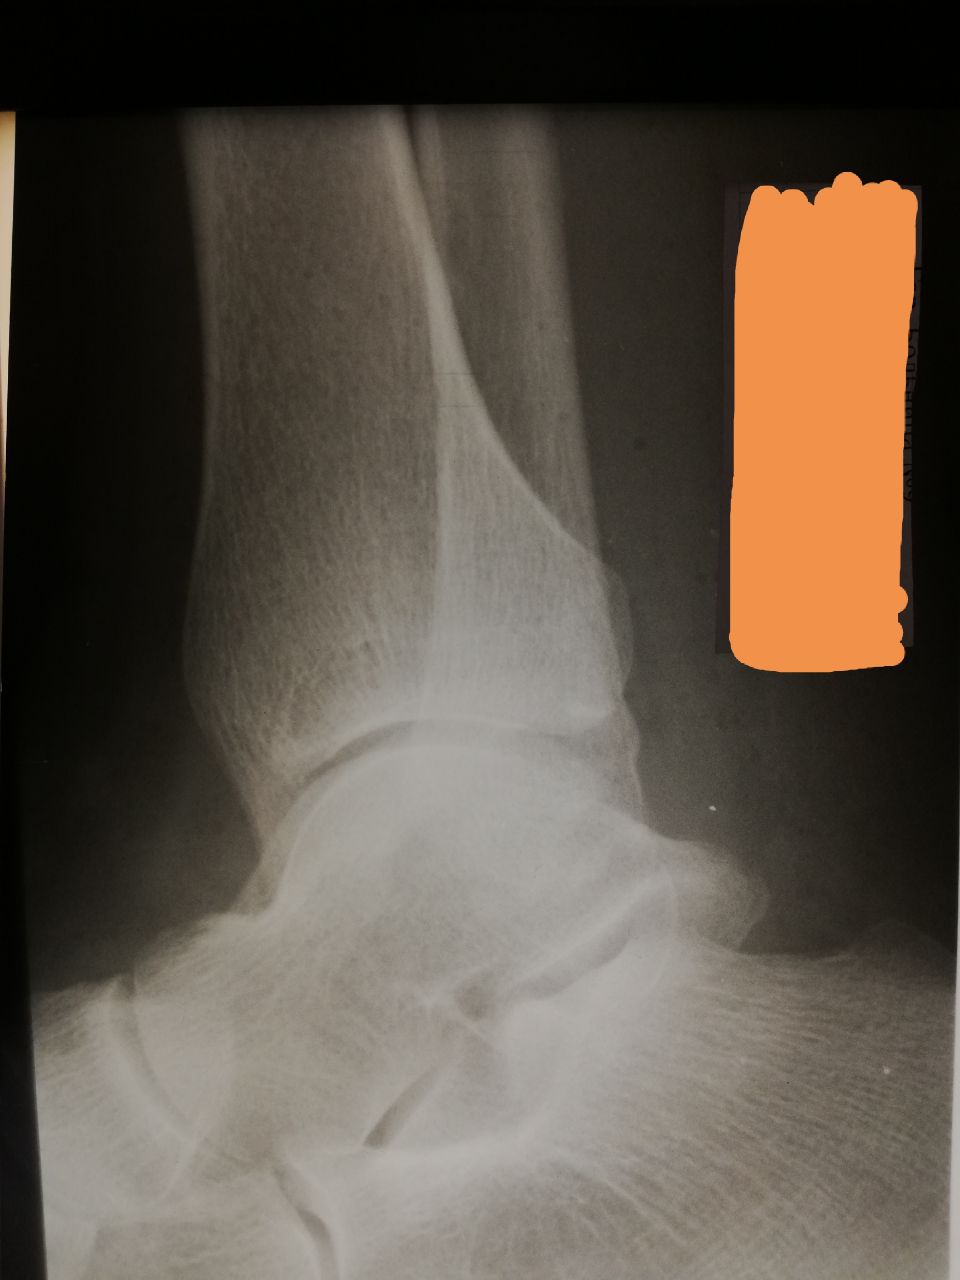

Сергей К in Radiology/Рентгенология Чат

Добрый вечер, уважаемые коллеги! Помогите, пожалуйста, с голеностопом. Мужчина, 50 лет, 10 дней назад была травма. Очень смущают обе лодыжки. Под латеральной - какой-то костный фрагмент, медиальная как будто тоже не очень ровная. Переломы? Добавочные кости?

Латеральная скорее всего старый перелом, больше ничего не вижу.